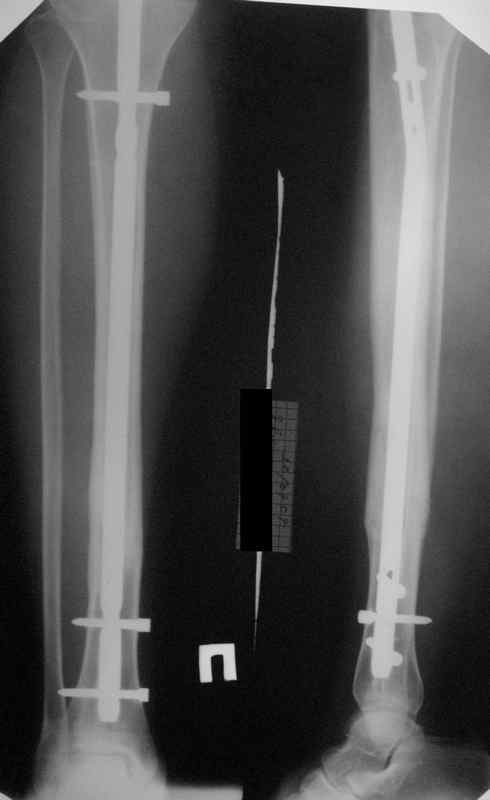

КА> Но почему решение динамизировать на сроке 8 недель с полным

В приложении картинка пациента со сломанным внизу гвоздем. Начал лечение в другом учреждении. Еще и адвокат к тому же.

Динамизировали через 8 недель, а оно поползло больше, чем хотелось бы.

Посмотрев на клинический случай с винтообразным переломом ББ и МБ костей, возник вопрос о целесообразности динамизации фиксатора при подобном типе перлома.

Винтообразный перелом создает обширную зону межфрагментарного контакта, что является благоприятным условием для консолидации, если в ожидаемые 8-10 недель мозолеообразования не наблюдается, то динамизация приводит к *соскальзыванию* проксимального фрагмента- вторичному смещению, величина которого и определяется размером овального окна гвоздя.

Логичным, на мой взгляд, в подобной ситуации является не динамизация гвоздя, а смена гвоздя на больший размер с рассверливанием.

Динамизация скорее показана при поперечных/ short oblique типах, когда зона межфрагментарного контакта ограничена, нет риска вторичного смещения отломков.